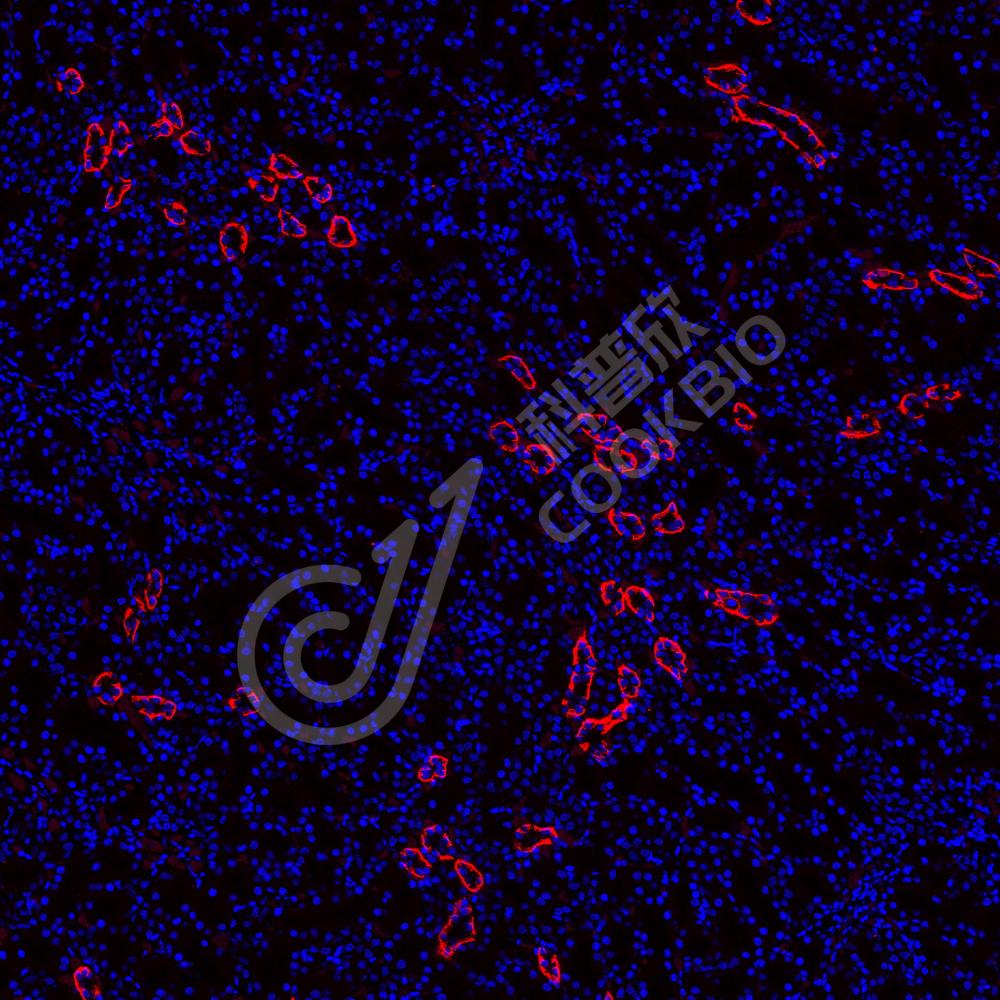

IF检测Aquaporin 4蛋白(货号 K546590)(红色).

样品: 小鼠肾, 4%多聚甲醛 (货号KSG1101) 固定12-24小时.

抗原修复: Tris-EDTA抗原修复液(pH 9.0) (货号KSG1203), 水浴100℃, 25分钟.

封闭: 3% BSA(货号KSGC305010)的PBS溶液, 室温孵育30分钟.

—抗: 1: 800稀释, 4℃ 孵育过夜.

二抗: Cy3标记山羊抗兔IgG (H+L) (货号KB63909), 1: 300稀释, 室温孵育1小时.